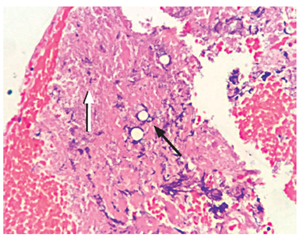

No hubo complicaciones relacionadas con el procedimiento (Figura 2). El reporte de histopatología fue la presencia de necrosis e inflamación, y a la coloración de Gomori-Grocott se evidenció la presencia de levaduras multigemantes de tamaño variable compatibles con paracoccidioidomicosis. La tinción de Ziehl-Neelsen fue negativa para bacilos ácido-alcohol resistentes y no se evidenció malignidad en la muestra (Figuras 3 y 4). El paciente recibió manejo con anfotericina B hasta completar el esquema y fue dado de alta por mejoría clínica evidente, con manejo ambulatorio con itraconazol y prednisona oral.

El diagnóstico definitivo se realiza con la visualización microscópica de células gigantes tipo Langhans y levaduras con gemación múltiple en patrón de timón de barco, con una mayor que tiene varias menores en gemación, en su periferia. Las tinciones del ácido peryódico de Schiff (PAS) y de plata permiten una mejor visualización de dicho hallazgo 6.